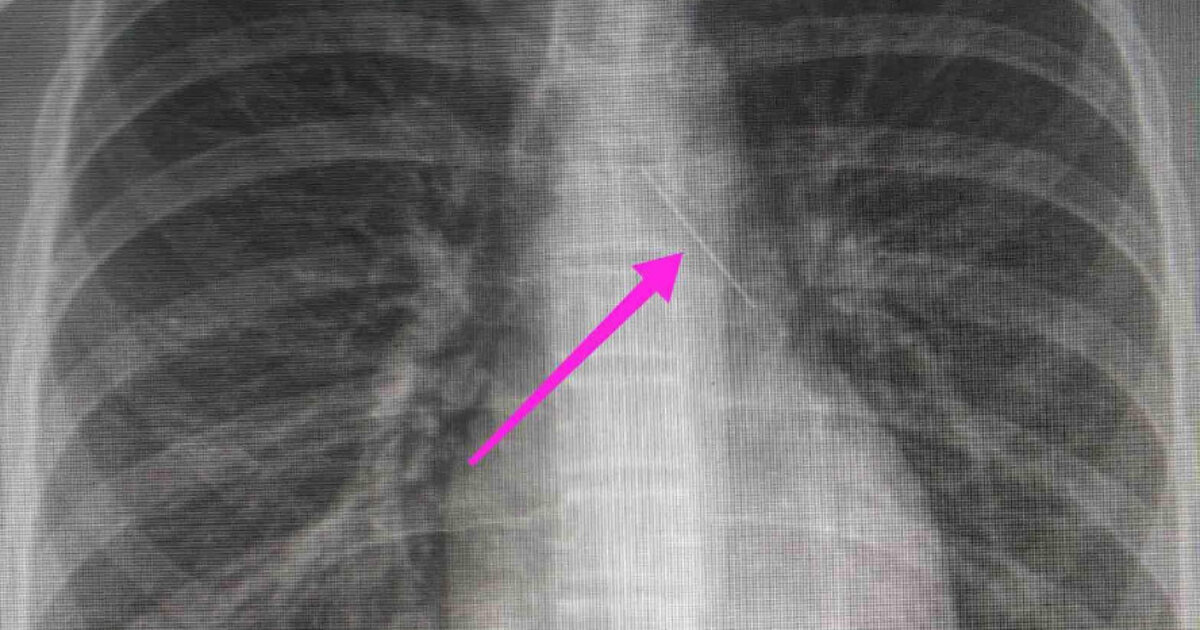

Σύμφωνα με ανάρτηση του νοσοκομείου στα μέσα κοινωνικής δικτύωσης, από την απεικονιστική διερεύνηση που πραγματοποιήθηκε με ακτινογραφία θώρακος αρχικά και ακολούθως με αξονική τομογραφία θώρακος, διαπιστώθηκε η ύπαρξη αιχμηρού μεταλλικού ξένου σώματος στην αναπνευστική οδό (αριστερός κύριος βρόγχος) και όχι στην πεπτική οδό.

Η ανήλικη υπεβλήθη σε βρογχοσκόπηση και διαπιστώθηκε η μετακίνηση και ενσφήνωση του ξένου σώματος στον δεξιό κύριο βρόγχο. Μετά οπό εργώδεις προσπάθειες ολοκληρώθηκε με επιτυχία η αφαίρεση της καρφίτσας.

“Χθες 30/1/2022 στις 16:00 στο Τ.Ε.Π. του ΓΝΘ Ιπποκράτειο, προσήλθε ανήλικη συνοδευόμενη από τους γονείς της, μετά από αναφερόμενη κατάποση ξένου σώματος (καρφίτσα). Από την απεικονιστική διερεύνηση που πραγματοποιήθηκε με ακτινογραφία θώρακος αρχικά και ακολούθως με αξονική τομογραφία θώρακος, διαπιστώθηκε η ύπαρξη αιχμηρού μεταλλικού ξένου σώματος στην αναπνευστική οδό (αριστερός κύριος βρόγχος) και όχι στην πεπτική οδό.

Πραγματοποιήθηκε πλήρης προεγχειρητικός έλεγχος και RAPID PCR (COVID-19), και μετά την λήψη συγκατάθεσης των γονέων που συνόδευαν την ασθενή, οδηγήθηκε στη χειρουργική αίθουσα. Μετά από την χορήγηση γενικής αναισθησίας από την ιατρό Αναισθησιολόγο, Διευθύντρια κα Μαρία Μυλωνά (για την διεκπεραίωση του ιδιαίτερου αυτού περιστατικού) υποβλήθηκε σε βρογχοσκόπηση με άκαμπτο βρογχοσκόπιο από τους Ιατρούς Ω.Ρ.Λ., Καρασμάνη Ηλία και Μαγγανάρη Αργύρη, Επιμ Α’ της ΩΡΛ Κλινικής του Γ.Ν.Θ. «Ιπποκράτειο».

Κατά την βρογχοσκόπηση διαπιστώθηκε η μετακίνηση και ενσφήνωση του ξένου σώματος στον δεξιό κύριο βρόγχο. Μετά οπό εργώδεις προσπάθειες ολοκληρώθηκε με επιτυχία η αφαίρεση αυτού. Η ασθενής ανένηψε πλήρως εντός της χειρουργικής αίθουσας. Η ασθενής μεταφέρθηκε για παρακολούθηση και νοσηλεία στη Γ’ Παιδιατρική Κλινική.